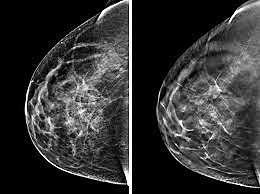

First Mammogram

Women ages 40-44 should have the choice to start annual mammogram screening for breast cancer. A mammogram is an x-ray of the breast, and are used to check for breast cancer in women who don't show any signs or symptoms of the disease. Mammograms usually involve two or more x-ray pictures of each breast. The images often make it possible to detect tumors that can't be felt.